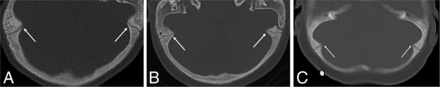

CT images show bilateral internal hypertrophy yet open occipital mastoid sutures (white arrows) in 3 different patients with MPS IH. A, This is the first patient with CT at the head bone window obtained at 1 year of age. B, This is the second patient with CT at the head bone window obtained at 1.6 years of age. C, This is the third patient with CT at the head bone window obtained at 1 year of age.

Skull sutures serve as sites of intramembranous bone growth, and their timed expansion allows brain growth.12 The fusion patterns vary depending on the suture, and particularly, the occipitomastoid suture only partially closes in <30% of healthy individuals and can stay open even in the ninth decade.13,14 Oussoren et al11 examined the incidence of early closure of major sutures in patients with mucopolysaccharidosis and showed that as many as 11 of 14 patients with MPS IH (71%) had early major suture closure resulting in craniosynostosis. However, to our knowledge, there is no study examining the minor sutures in patients with MPS IH. While CT scans were not commonly performed in our cohort, we found 3 separate cases with large posterior fossa horns and open occipitomastoid sutures, suggesting that the prominence of the posterior horn was not due to early suture closure as postulated in the early study involving major sutures but rather likely due to the effects of MPS IH (Fig 2).